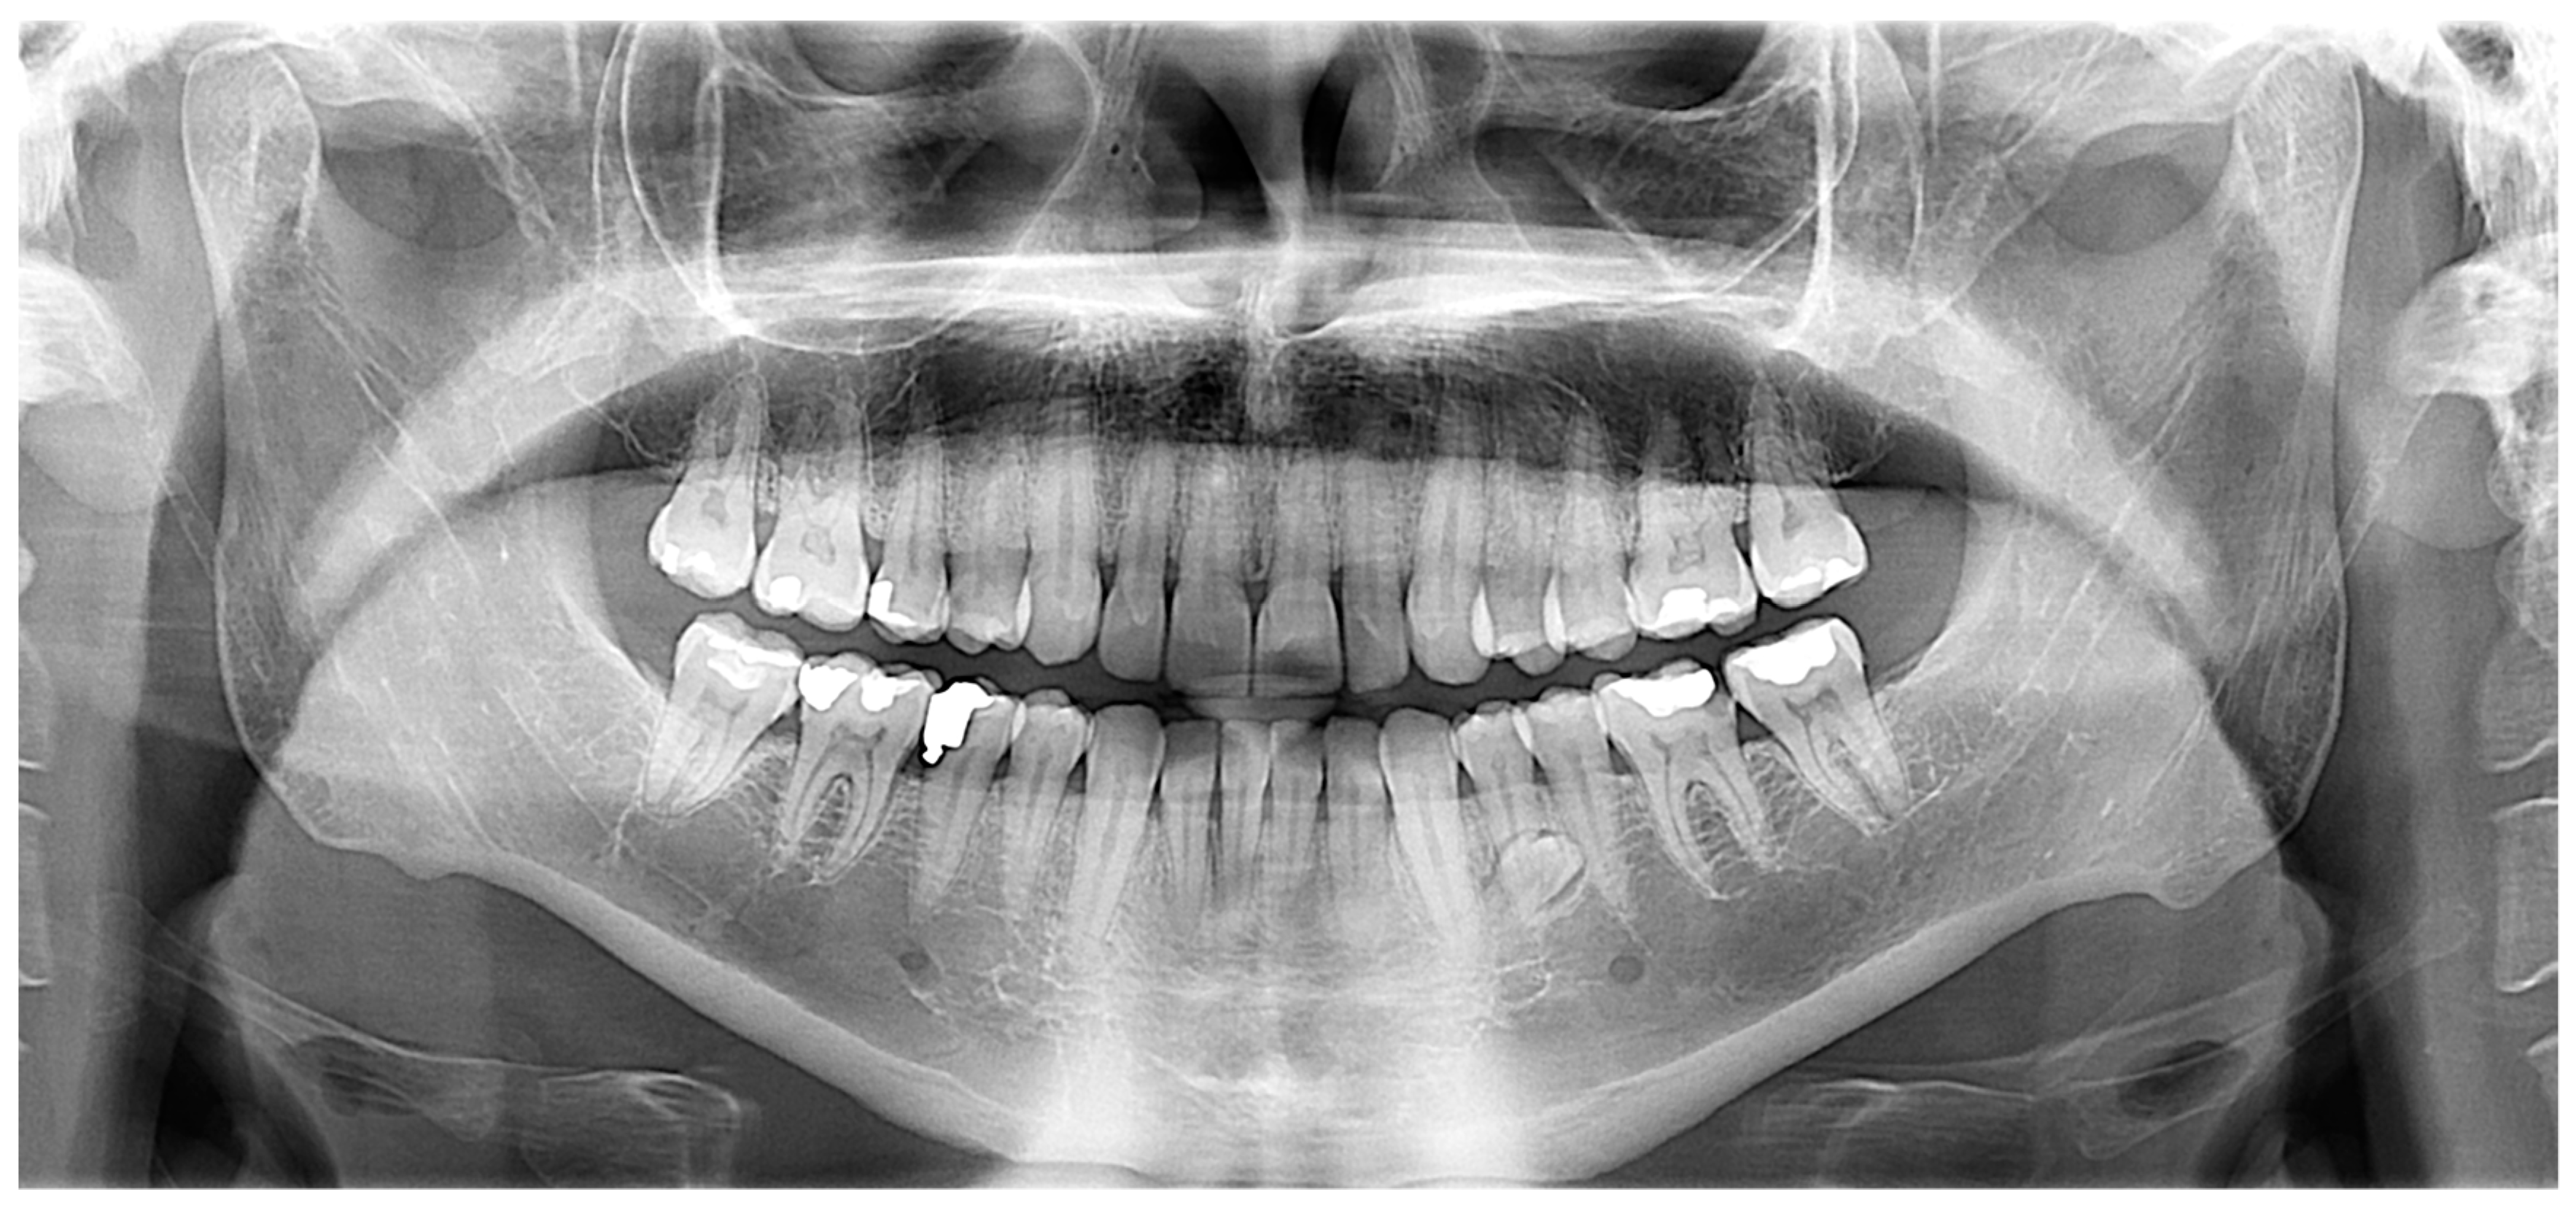

2.1. Case 1

Case 1 Presentation